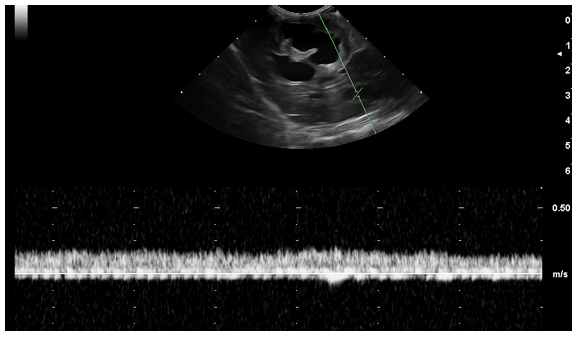

An ultrasonographic re-examination performed at 4 weeks showed a decrease in the intrahepatic bile duct size, however, transversal intraluminal septae at the level of the intrahepatic biliary tree were noted (Figure 5-white arrow). Portal flow velocity was recorded within normal limits, with regular flow (Figure 6).

Figure 6 Transverse image of the portal flow velocity (20 cm/s). Normal portal vein wave was present.

Even though portal flow was recorded as turbulent when first diagnosed, velocity became normal, a possible relation to the adaptive physiological mechanisms.

Furthermore, as the disease advances, transverse septae at the level of the bile ducts, gallbladder rim, and thickening of the biliary tree have been noted. Even if the initial PW Doppler recorded turbulent flow, follow-up examinations showed normal velocity of the portal vasculature. This may be in relation to treatment response or adaptive physiological mechanisms. Imaging modalities can be used to describe and monitor Caroli's disease, biliary tree changes, and cysts at the level of abdominal organs, but also as a response to symptomatic treatment.